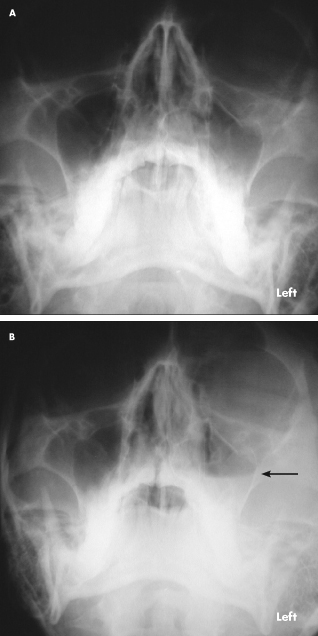

Orbital Floor Fracture

Four hours before he arrived at the emergency department, a 33-year-old man had been struck in the face by a rock. A laceration and periorbital hematoma were noted on the left side of the patient’s face. He complained of pain in this area. There was no history of intraocular disease. The left globe was intact, and no neurologic deficit was found.

A supine radiograph demonstrated interruption and widening of the floor of the left orbit (A). An upright radiograph revealed fluid in the left maxillary sinus (B, arrow), consistent with hemorrhage. Orbital floor fracture was diagnosed.

An axial CT scan of the orbits demonstrated widening and increased density in the periorbital fat, which indicated soft tissue swelling (C). The scan was performed to evaluate the medial and lateral walls of the orbit, which were determined to be intact.

A direct coronal CT scan showed the depressed fracture of the orbit floor, hemorrhagic debris in the left maxillary sinus (D, white arrow), and intraorbital emphysema (D, red arrow); air was noted passing through the fracture from the left maxillary sinus into the left orbit. Coronal imaging is best for visualizing the roof and floor of the orbit. If direct coronal imaging cannot be performed, thin-section axial images can be obtained with generation of coronal reformats.

Orbital floor fractures may be caused by direct trauma to the inferior orbital rim, which results in buckling of the orbital floor. Fractures may also occur when rapidly increased intraorbital pressure is decompressed at the weakest point of the bony confines of the orbit.

Suspect an orbital fracture when a patient has a history of trauma, ecchymosis with or without edema of the lids, diplopia, hypoesthesia of the cheek (related to injury to the infraorbital nerve), or emphysema of the orbit or lids. Enophthalmos and ptosis of the globe indicate a large fracture.

Fractures of the orbit frequently involve the weakest part of the bony orbit—the lamina papyracea or medial wall. If the medial wall is involved, hemorrhagic debris is seen in the ethmoid complex, and air that emanates from the ethmoid results in intraorbital emphysema.

Fractures of the orbit roof and lateral wall are much less common. They can be complicated by cerebrospinal fluid leak and herniation of intracranial contents into the orbit; entrapment of the superior rectus muscle is rare.

Most orbital floor fractures heal without treatment, as in this case. Consider surgical repair in the event of complications, such as sensory disturbance as a result of injury of the infraorbital nerve, muscle entrapment when the inferior rectus herniates through the fracture defect, and enophthalmos from herniation of large portions of orbit contents into an adjacent sinus.